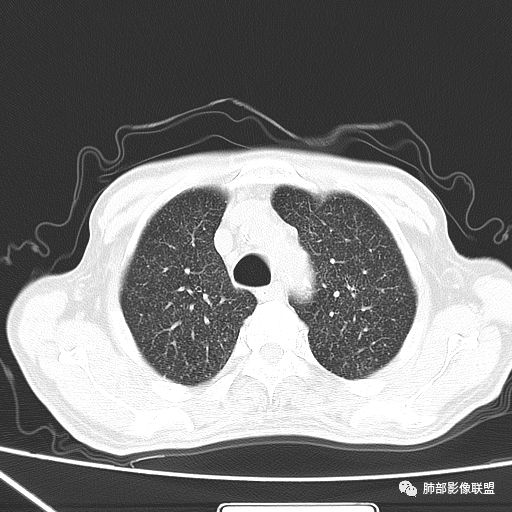

2019-10-20复查CT如下:

两肺弥漫性粟粒样结节伴左上肺小结节,呈三均匀分布,有结核的临床表现,支持血性播散性肺结核。

大小、分布均匀,边缘清楚

细小结节,弥漫,撒米粒样——血道来源

血道来源的病灶,均匀、细微,而且部分有分支状,都符合粟粒型肺结核

10月20日的CT其实是抗痨治疗近1月复查的CT。患者来我院后抗痨治疗体温下降,症状明显好转。

急性血行播散型肺结核  两肺广泛分布粟粒大小的结节状密度增高影,具有大小均匀、分布均匀、密度均匀的典型“三均匀”特征,注意急性血播病灶非常小,一般粟粒影直径1~2mm。

病灶密集者出现肺外围血管影不清或减少。

发热初期肺部可缺乏典型影像学改变,1到2周后出现的广泛粟粒结节对诊断具有高度提示作用!